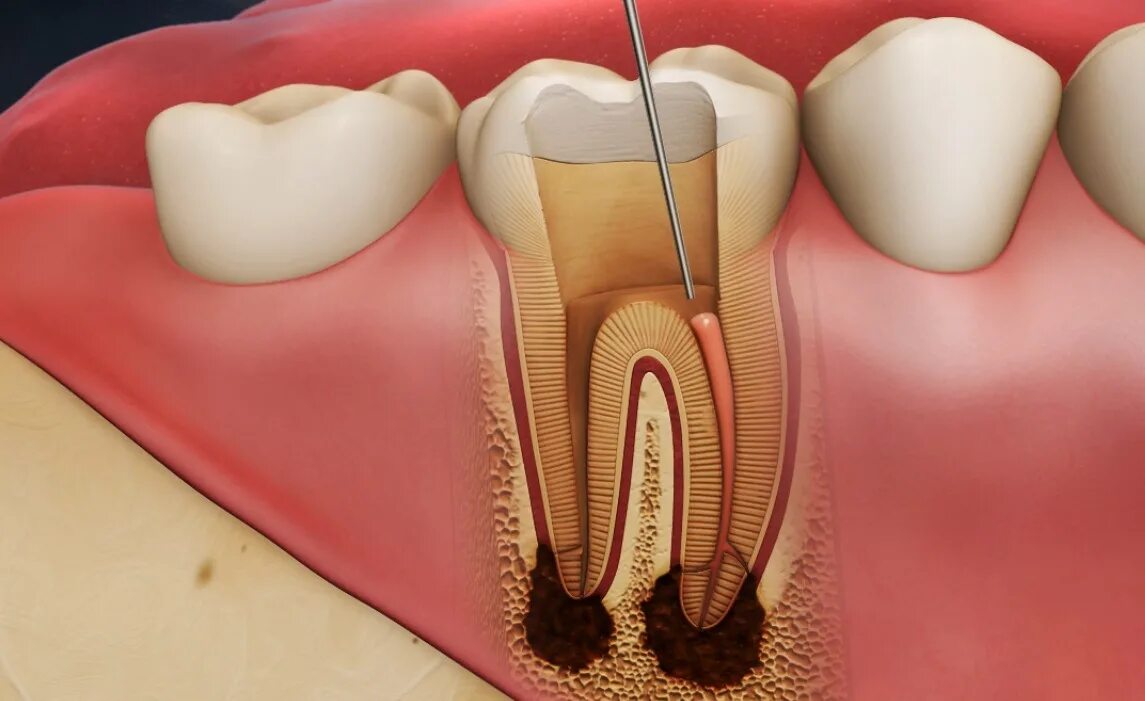

Лечение пульпита с несформированными